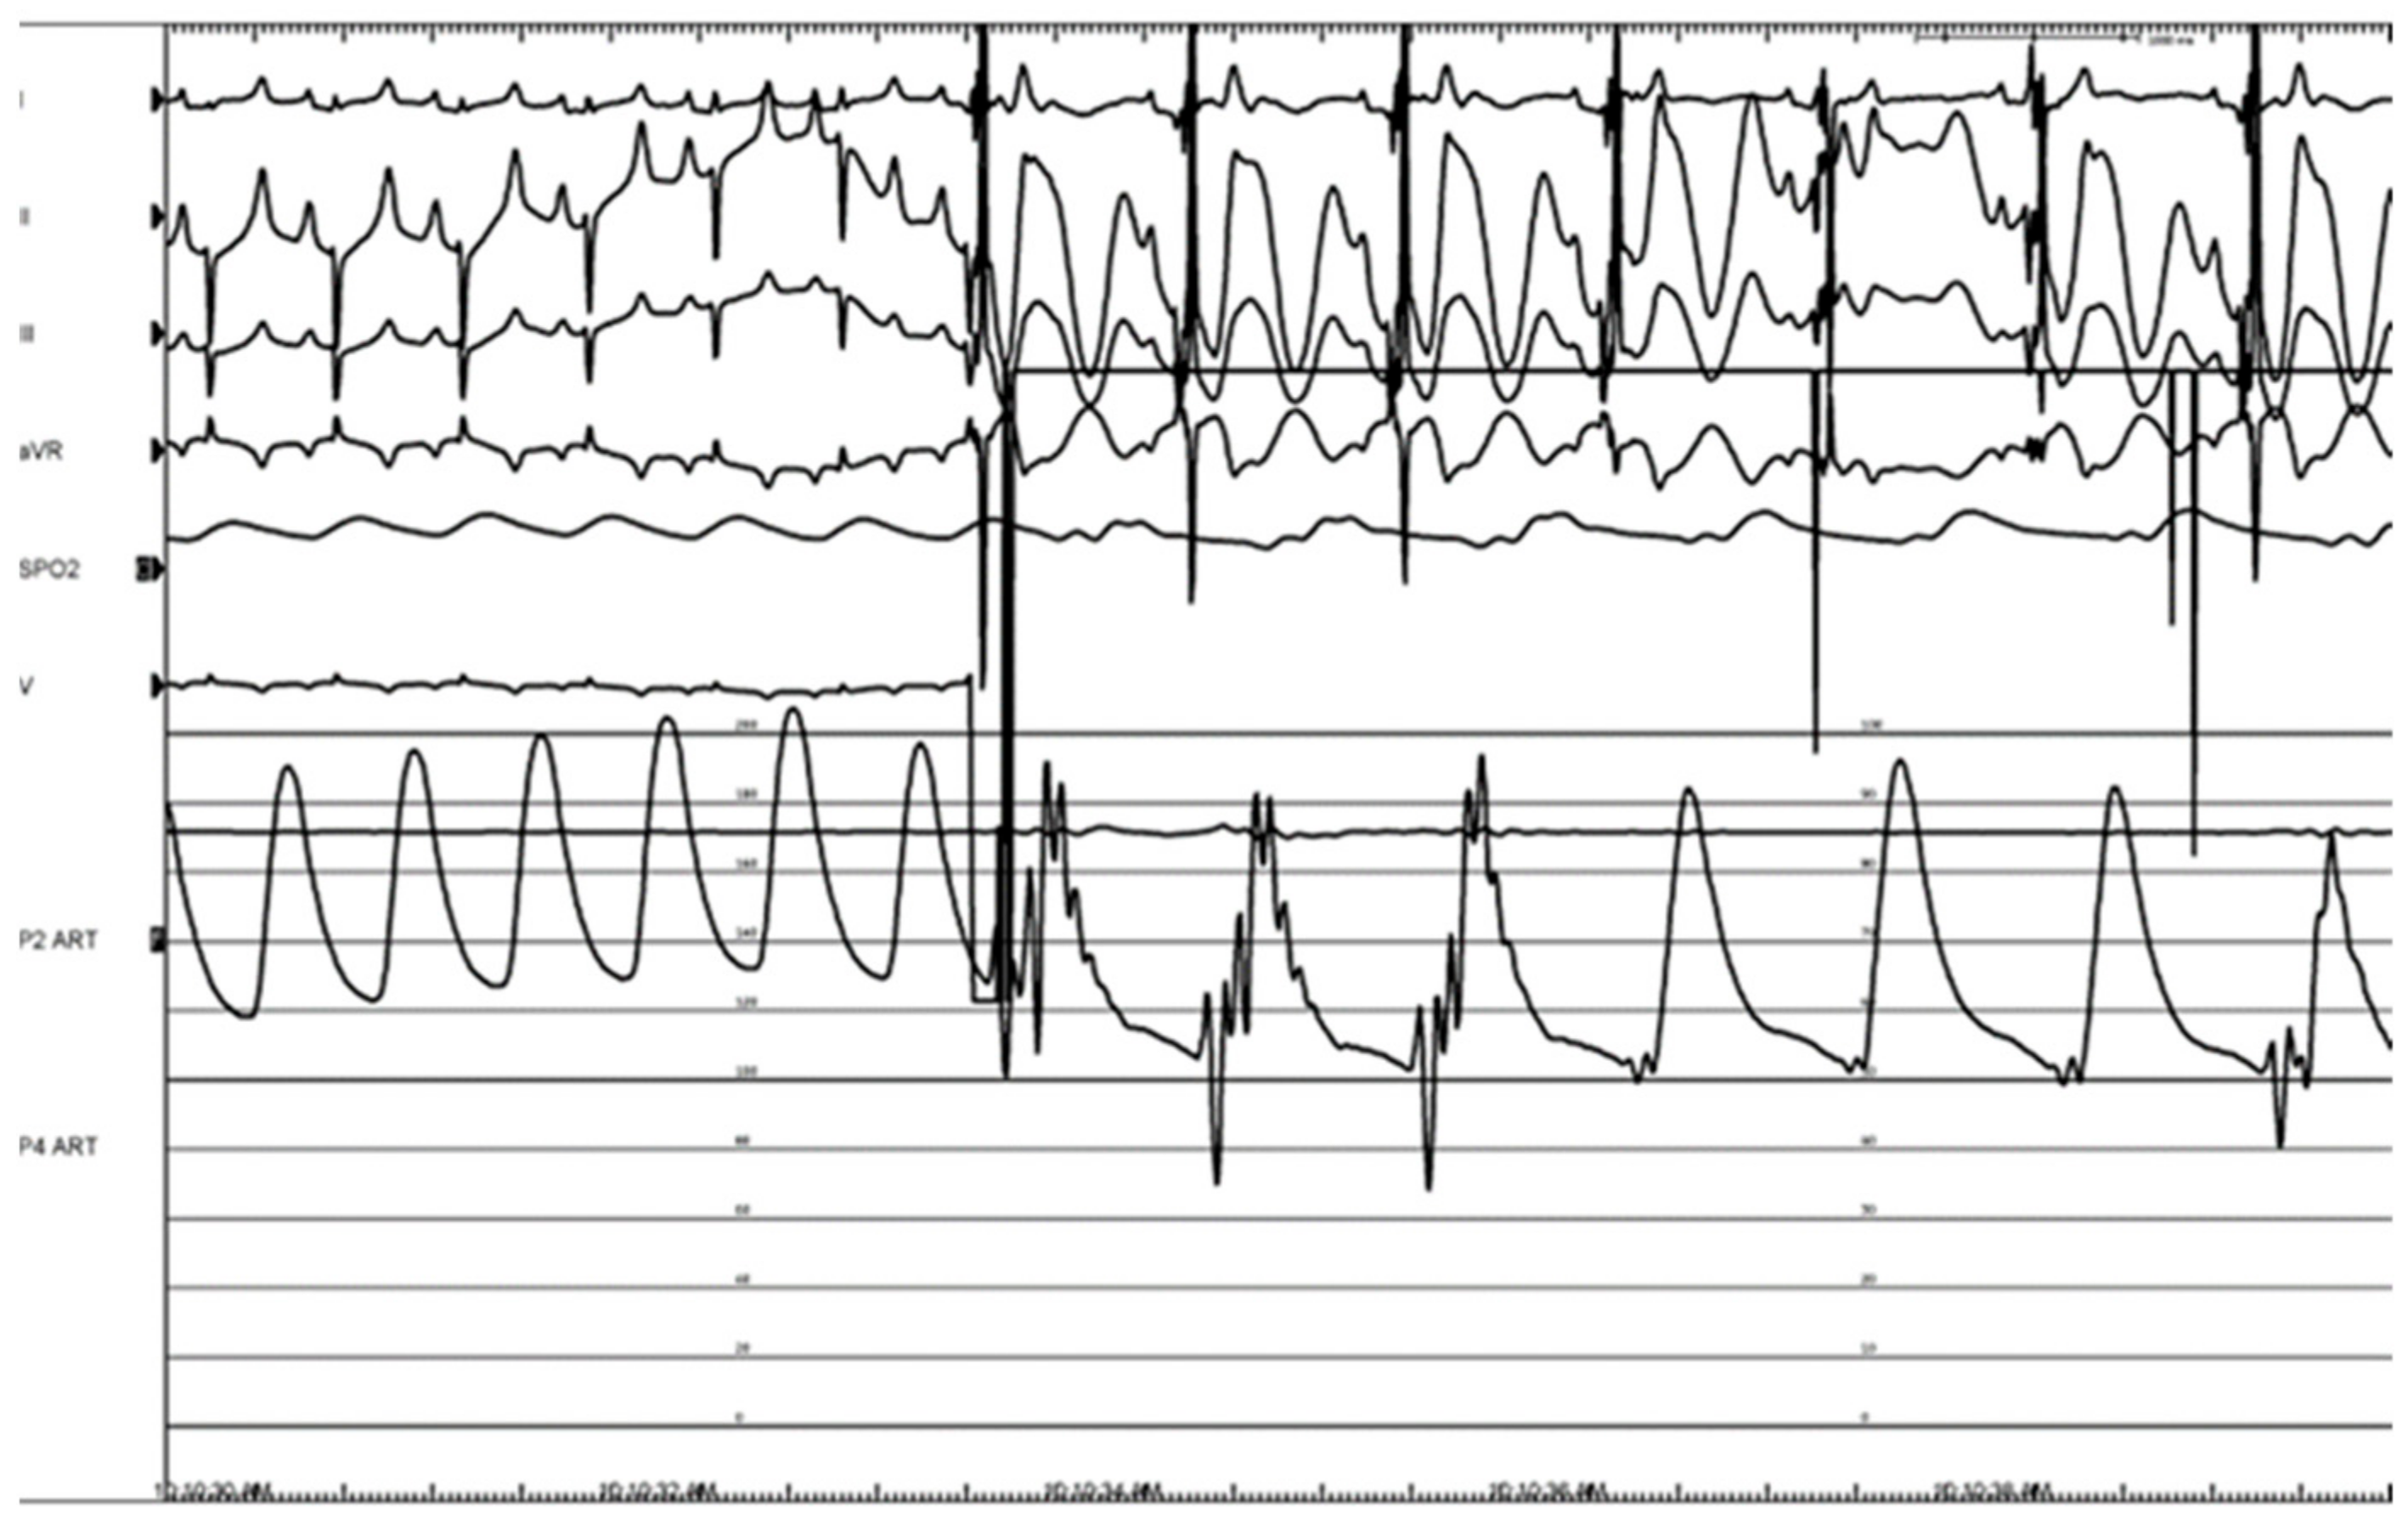

3.3. Histologic Evaluation

3.4. Porcine Study—Catheter Access and Navigation